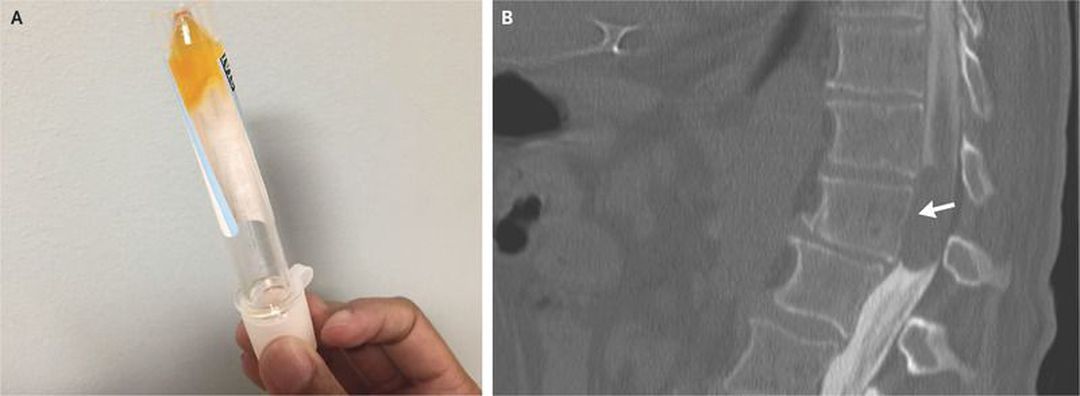

A 64-year-old man presented with a 1-week history of progressive bilateral weakness in the legs. The neurologic examination showed paralysis of the legs and decreased sensation starting at the L1–L2 level. Magnetic resonance imaging could not be performed owing to the presence of a pacemaker. Since the patient had atrial fibrillation and an elevated prothrombin time, there was concern about a possible spinal hematoma. Computed tomography (CT) of the spine showed only degenerative disk disease. On lumbar puncture, the cerebrospinal fluid (CSF) was xanthochromic, viscous, and coagulated in the tube (Panel A). The protein level in the CSF was more than 1500 mg per deciliter, and the glucose level was 45 mg per deciliter (2.5 mmol per liter). The CSF contained less than one nucleated cell per cubic millimeter, and the results of Gram’s staining and cultures were negative. The combination of elevated protein, xanthochromia, and hypercoagulation of CSF is pathognomonic for Froin’s syndrome, which can occur with blockage of CSF flow by a spinal cord mass or with meningeal irritation from meningitis. CT myelography showed a large intradural, extramedullary lesion at T11–T12 (Panel B, arrow), which was compressing the spinal cord. The patient underwent total laminectomy of T11 and T12 and partial laminectomy of L1 with tumor resection; a benign nerve-sheath tumor (schwannoma) was diagnosed on pathological analysis. No radiotherapy or chemotherapy was performed. After 1 month of rehabilitation, the patient had improved sensation but continued having leg paralysis.